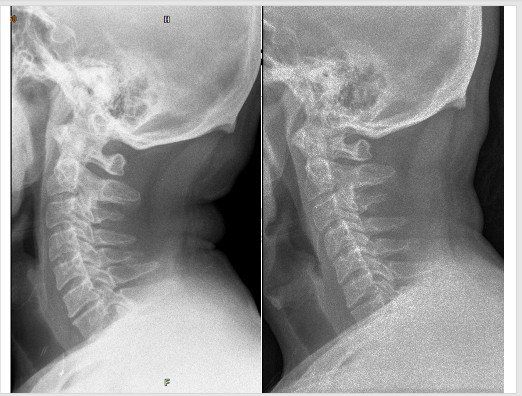

ื"ืจ ื ืืืื ืงืืืข ืืช ืชืืื ืืช ืืืืคืื ืืืืืืฆืช ืืืชืื ืืืกืืืจืื ืืจืคืืืืช, ืืืฆืื ืืืืืงืืช, ืืืฆืื ืจื ืืื, ืกื-ืื ืื ืื-ืืจ-ืืื, ืืืฉืืฉ ืืืืืืช ืืืืืืจ ืฉื ืคืืข ืืืืืื ืืืจืืคืจืงืื ืืื ืืืขืจืื ืขื ืืื ืืฉืคืืข ืื ืืง ืืขืืื ืืฉืืืจื ืขื ืืขืจืืช ืืขืฆืืื ืืืจืืืืช ืืืืฃ. ืืฉืื ืืืืืจ ืฉืชืคืงืื ืืืืจืืคืจืงื ืืื ืืืกืืจ ืกืืืืงืกืฆืื (ืชืช ื ืงืืขื ืฉืืจืชื) ืฉืืคืจืืข ืืืืฃ ืืชืคืงื ืืืืคื ืืืคืืืืื. ืชืืืื ืจืืคืื ืืจืงืืืช ืืื ืืืขื ืืืชืืคืฉืจ ืืชืื ืืืืฃ ืขืฆืื. ืืืืฃ ืืฉ ืืืืืช ืจืืคืื ืืืขืืช ืืืืืืขืช ืืืจืงื ืืื ืื ืืฉืื. ืืืืืื ืืืืจืืคืจืงืื ืืกืืจ ืืืฅ ืืืืขืจืืช ืืขืฆืืืช ืข"ื ืฉืืคืืจ ืชืคืงืื ืขืืื ืืฉืืจื, ืืืืคืฉืจ ืืื ืจืืื ืืขืฆืืืช ืืืฉืชืืฉ ืืืืืืืช ืืืืฃ ืืืืขืืืช ืืืืืื. ืจืคืืื ืืืชืืช ืชืืื ืืื ืืืื ืืืืื ืืชืื ืืืืฃ ืขืฆืื. ืชืงืฉืืจืช ืืื ืืืื ืืืืฃ ืืืืจื ืืื ืืืืฃ ืืืื ืืืื ืืช ืืงืืื ืืืืฃ ืืืจืืืืชื. ืคืืื ืฆืืื ืืืจืืืืช ืืืืืช ืื ืจืืืืช ืืืืื ืฉืืืืฃ ืืืื ืืืืืข ืชืืืืื ืืืจืืืืช ืขืืื ืืฉืืจื ืืืืขืจืืช ืืขืฆืืืช ืฉืคืืขืืื ืืื ืืคืจืขืืช ืืืชืืื.

ืืืืคืื ืืืืจืืคืจืงืื ืืืื ืืช ืืืืฃ ืืืืจืืฅ ืืช ืื ืจืืืืช ืืืืื ืืชืืื ืืืืืื.